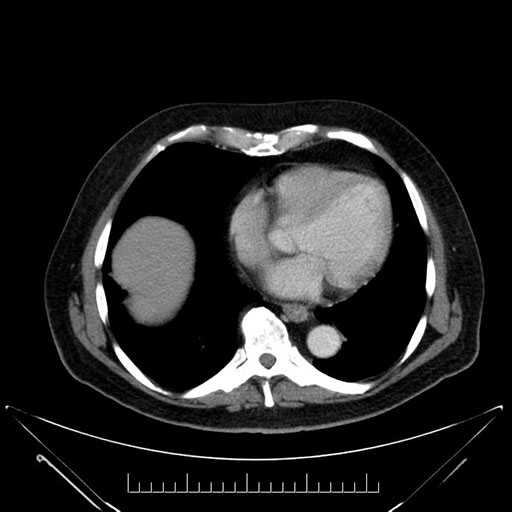

Imaging Analysis

Look through the patient's CT scan to identify any areas of concern for the necessary procedure.

Based on your CT findings, which issue(s) would give reason for "planned slowing down moment(s)" in this case?